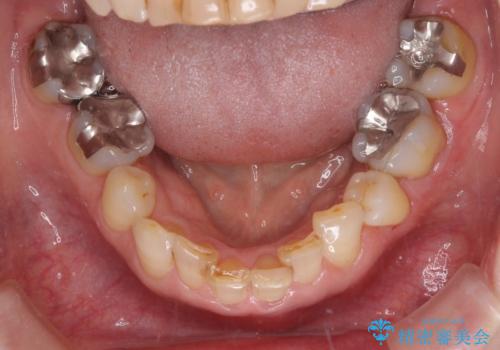

- 下顎前歯が痛んで近医を受診したところ、下顎前歯2本を抜歯してインプラント治療が必要と診断されたとのことで来院された患者様です。

診査の結果、下顎左側中切歯の神経が失活していることが痛みの原因であり、根管治療を行う必要があると診断されました。

根管治療を行った後にオールセラミッククラウンにて補綴することとしました。

隣在歯にも根尖部の炎症が及んでいるように見えましたが、術前診査では神経が失活している様子がなかったため、まずは原因歯から処置を行うこととしました。

初回の根管治療後には痛みが速やかに改善し、6か月後のレントゲン写真では根尖の病変が消失していることが確認できました。